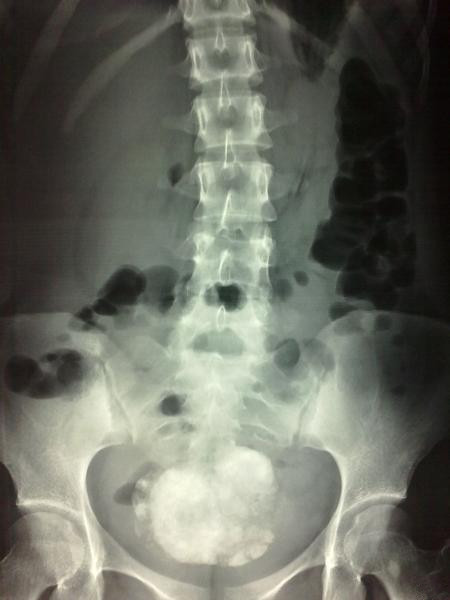

查体:生命体征平稳,心肺无特殊,下腹部压痛轻,中下腹部反跳痛明显。未扪及包块。 辅助检查:血常规正常,凝血正常。彩超:右下腹部短杆样肠管改变。子宫及附件无异常。肝胆脾无异常。腹部立卧位:不完全性肠梗阻,盆腔占位。

入院后保守治疗,患者症状无明显缓解,与患者及家属沟通,行剖腹探查术,术中发现该肿物发自右侧卵巢,呈带蒂装,肿物大小约12cm*8cm*5cm,边界清楚,质地硬,可见骨骼样组织。术中考虑是畸胎瘤。肿物送病理检查。